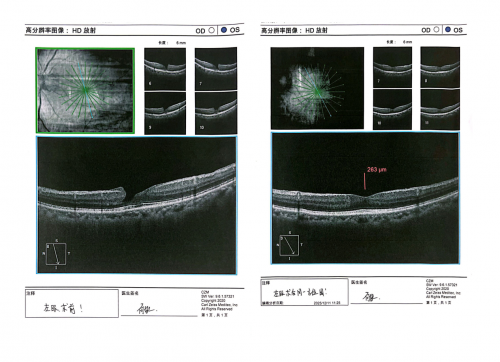

术后第五天,黄先生准时从香港来到深圳复查。眼底照相、光学相干断层扫描的影像上,除了眼球腔内上方还残余少部分气体外,看不到任何手术痕迹。濒临全层破裂的黄斑裂孔,也已完美闭合,图像上看好像不曾病变过!

视力表前,黄先生轻松读出了 1.0 的视标,双眼视力均为最佳理想状态。

赵铁英院长复查时,看着黄先生的复查报告也露出欣慰笑容:“手术过程安全、顺利,术后黄斑组织结构及功能的恢复状态堪称完美,效果远超预期,再过2~3天气体完全吸收,一切活动就都恢复正常了。